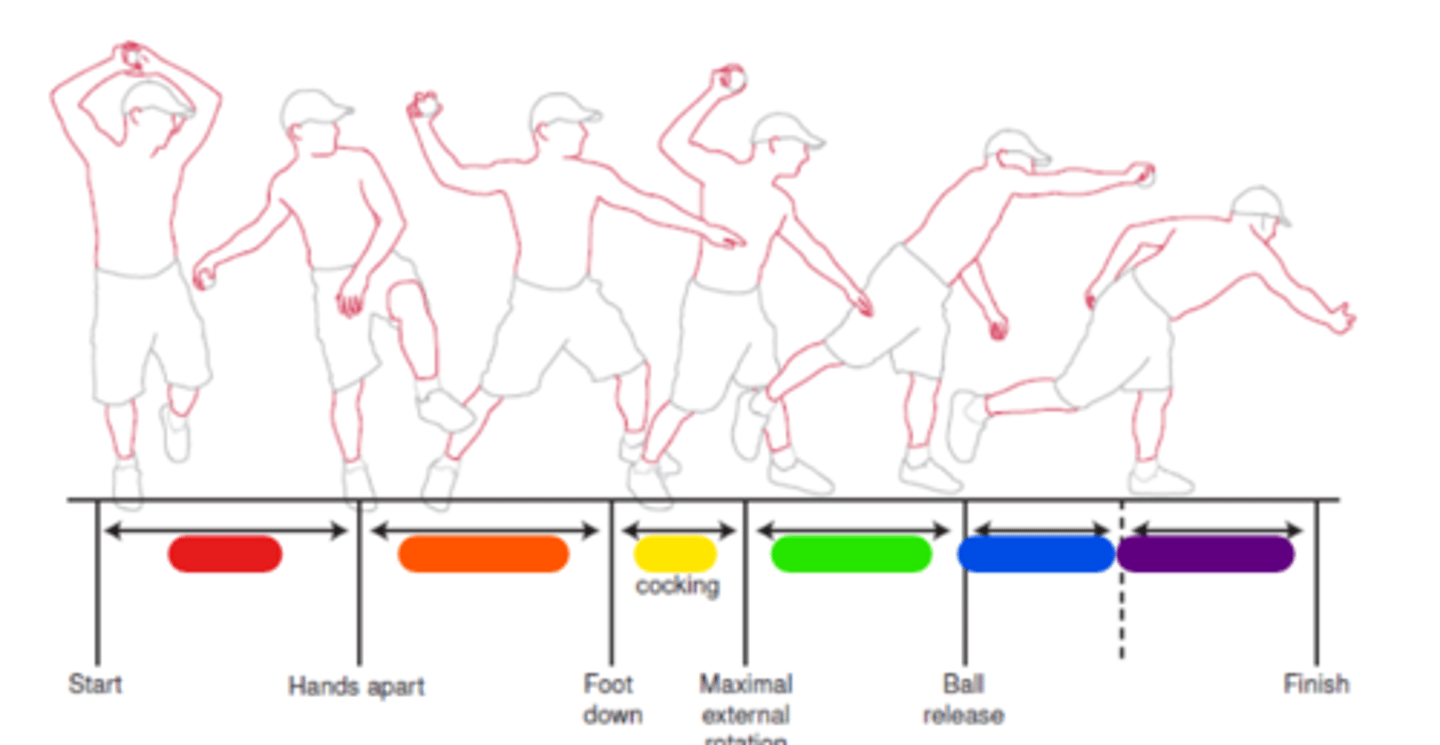

Windup

Red in image.

Early cocking

Orange in image.

Late cocking

Yellow in image.

Acceleration

Green in image.

Deceleration

Blue in image.

Follow through

Purple in image.